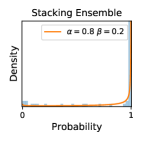

To model how different classifiers will respond to a given input , we assume that the prediction from classifier is sampled from a beta distribution that is characterized by two parameters by and . We further assume that is fixed to the same constant value for all ’s. Under this assumption, each input can be described by ( can be calculated since is fixed), easing further analysis. The Severity Level (SL) of the case represented by image can be characterized by the parameter . The larger the value of , the more severe the case of is. When and are close, the case is ambiguous as the distribution shifts towards being symmetric (i.e. signifying much disagreement among classifiers) rather than being one-sided (i.e. consensus among classifiers that is negative or positive). We provide a set of examples in Figure 2 and also Figure S.8 in the supplementary materials showing how the beta distribution can be used to capture diverse predictions given by an ensemble learner.

We conducted a case study on diagnosing diabetic retinopathy with ensembles of DL models. For benchmarking the performance of our ensemble-based solutions under the scheme described in Sec.3.3, we used two popular collections of diabetic retinopathy image data, the Kaggle Diabetic Retinopathy dataset [22] (hereafter referred to as “Kaggle-DR”) and the Messidor-2 dataset [23], each respectively consisting of and high resolution images. Diabetic retinopathy is graded into five SLs, as displayed in Figure 2. Following the problem setup used in previous papers [24], we trained models to distinguish the referable (SL2-4) cases from the non-referable ones (SL0 & SL1) (see Section B.1 for more detailed descriptions). We also tested our trained ensemble models on two o.o.d. image datasets (ImageNet [25] and CIFAR-10 [26]) to examine their capabilities of identifying o.o.d. inputs (see Section B in the supplementary materials).

Three types of ensemble methods (stacking ensemble, MC-dropout and TTA) described in Section 3.1 were evaluated in our experiments. We did not adopt the deep ensemble approach [1] in our case study because we did not manage to train the networks from scratch (random initialization). Our solution was to train all the models by reusing the weights from a pretrained ImageNet model, which proved to work well but also prevented us from implementing the original deep ensemble approach [1].

Our stacking ensemble models consisted of networks of two architectures (resnet34 [27] and VGG16 [28]). To induce diversity, we trained the networks using different subset of images (as in bagging [29]), images of different resolutions, training-time data augmentation strategies, and number of training epochs (as in snapshot ensembles [11]). MC-dropout ensembles and TTA ensembles are created during test time by repeatedly sampling the trained networks.

Comparing the three ensemble methods in Figure 4, the stacking ensemble method has the highest ratios of SL1 & SL2 data among the high-uncertainty examples it identified under both mean and var. TTA showed slightly better performance than MC-dropout but still falls behind the stacking ensemble method. Considering the fact that SL0 examples accounted for the majority of the dataset, the stacking ensemble method was much more precise (specific) in selecting truly ambiguous data points that were difficult to classify. From Figure 3, we can also see that the stacking ensemble method greatly outperformed the other two methods in finding false negatives under both mean and var uncertainty metrics.